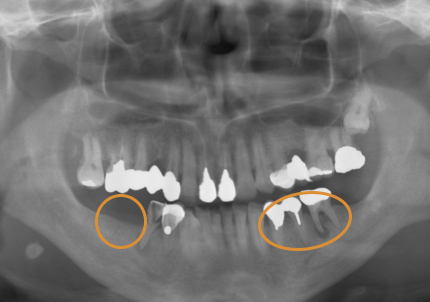

患者:S.G様(55歳/男性)

初診日 :2014年6月10日

主訴 :義歯が嫌いで使わず奥歯が咬めないので、全体の治療を希望する

1.初診時口腔内写真(2014年6月)

3.前回治療後5年経過(2021年2月)

【左下ブリッジ5番6番歯根破折の為要抜歯】

【左下5番ソケットシールドテクニック】